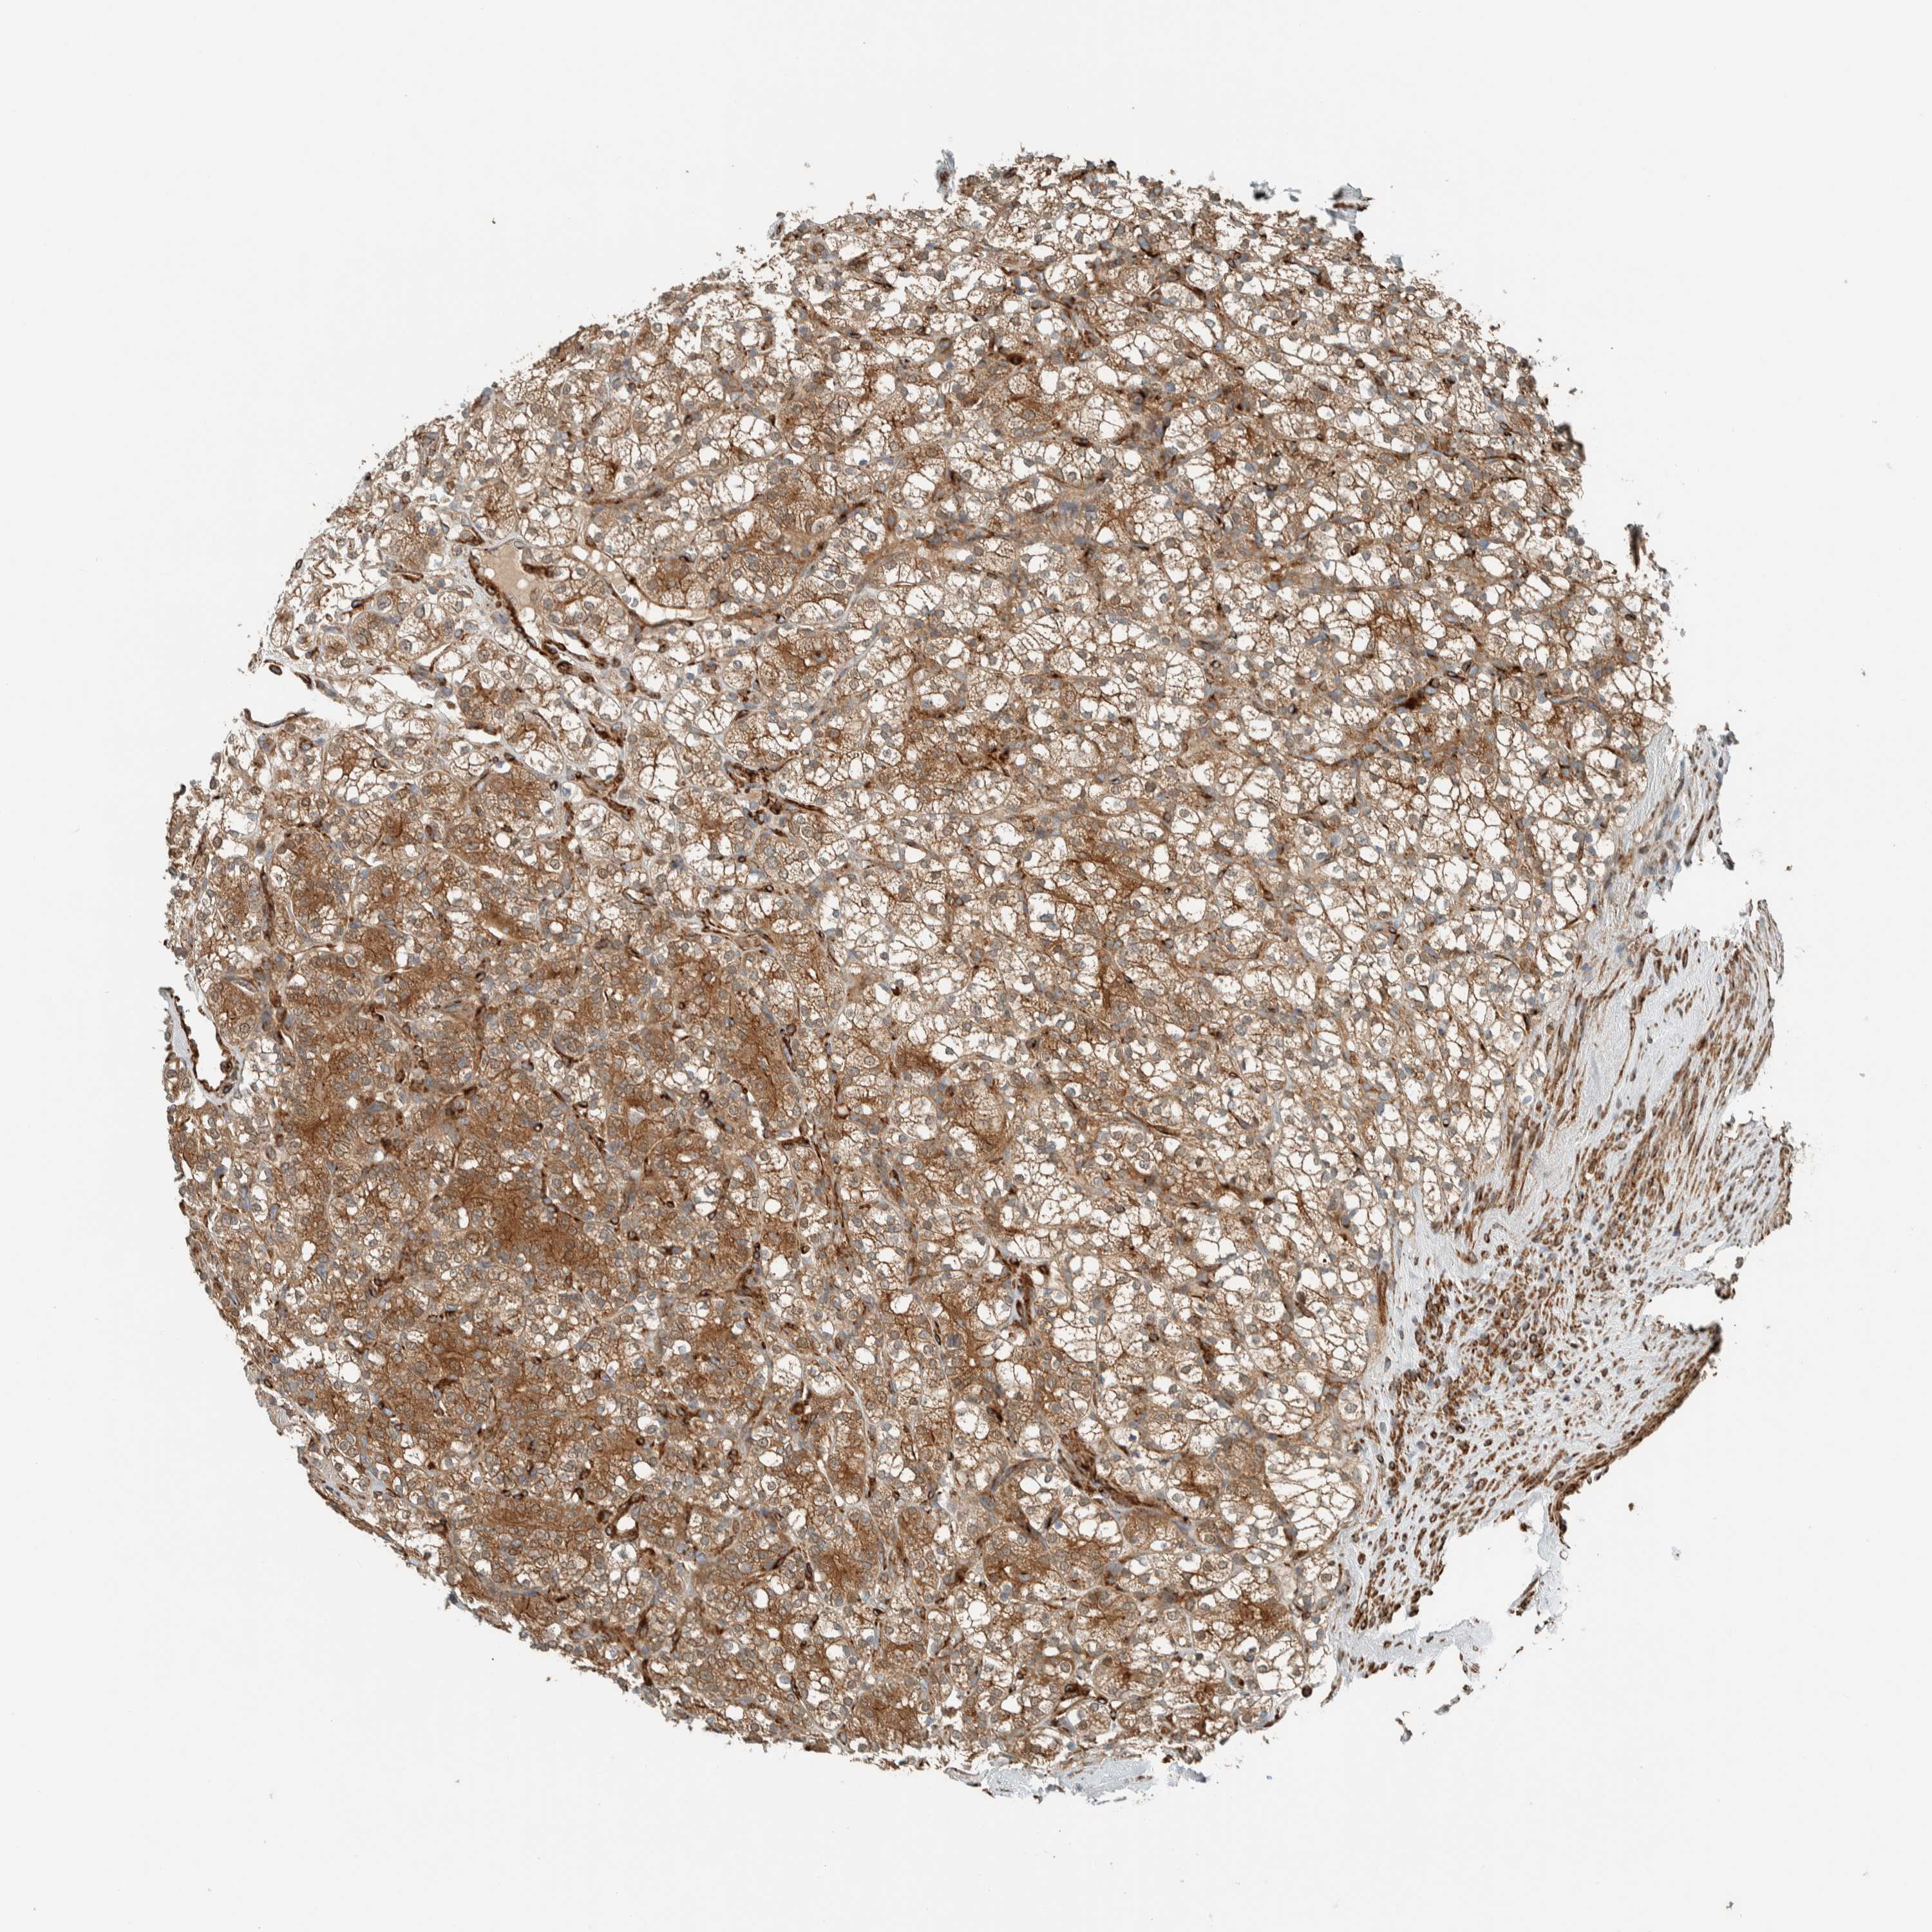

TCGA RNA samplesi

RNA-seq data is reported as average FPKM (number Fragments Per Kilobase of exon per Million reads), generated by the The Cancer Genome Atlas (TCGA) .

Normal distribution across the dataset is visualized with box plots, shown as median and 25th and 75th percentiles. Points are displayed as outliers if they are above or below 1.5 times the interquartile range. FPKM values of the individual samples are presented next to the box plot.

Average pTPM 52.2